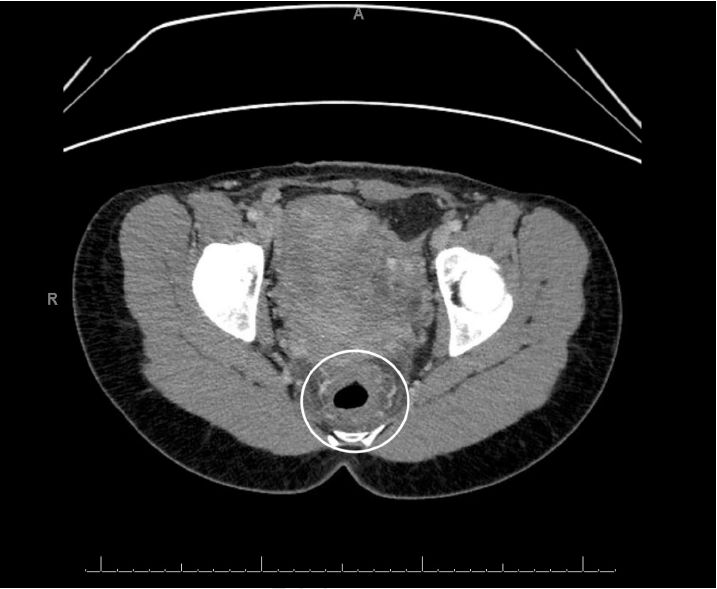

HIV和粪便检查结果为阴性。腹部和骨盆的计算机断层扫描(CT)扫描提示了异常发现(图A,图B),因此,我们又用内窥镜对患者进行了检查。在接下来的几天,乙状结肠镜检查的结果如图C、图D和图E。

腹部和骨盆的CT显示直肠壁增厚,提示直肠的炎症和充血,即直肠炎(图A,B)。乙状结肠镜检查的结果显示直肠和远端乙状结肠内的粘膜严重充血,伴随弥漫性红点(图C,D)与表面渗出物,且直肠和乙状结肠远端的粘膜脆弱。这些发现与化学直肠炎,特别是过氧化氢诱导的化学直肠炎的表现一致。